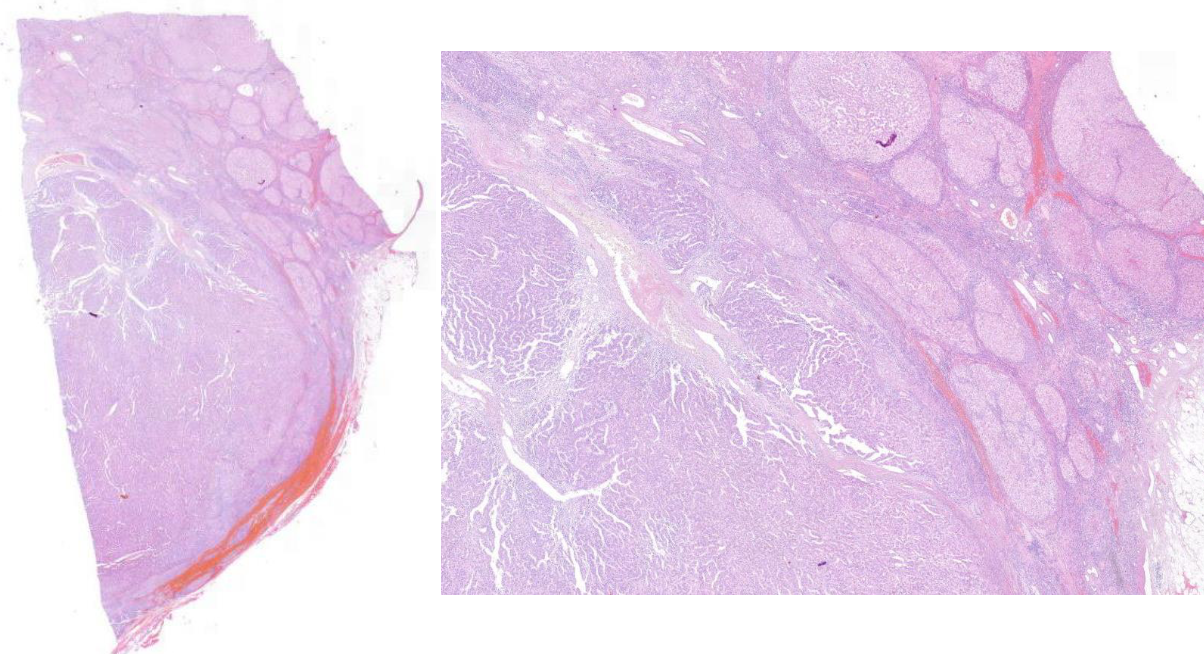

Diagnose?

Pleomorphes Speicheldrüsenadenom = BENIGNE

80% in der Parotis -> nicht destruktiv, nicht invasiv, nur verdrängend

v.a .Parotis, benigne, aufgebaut aus bindegewebiger Kapsel und epithelialen und mesenchymalen Gewebe (v.a. Knorpelgewebe)